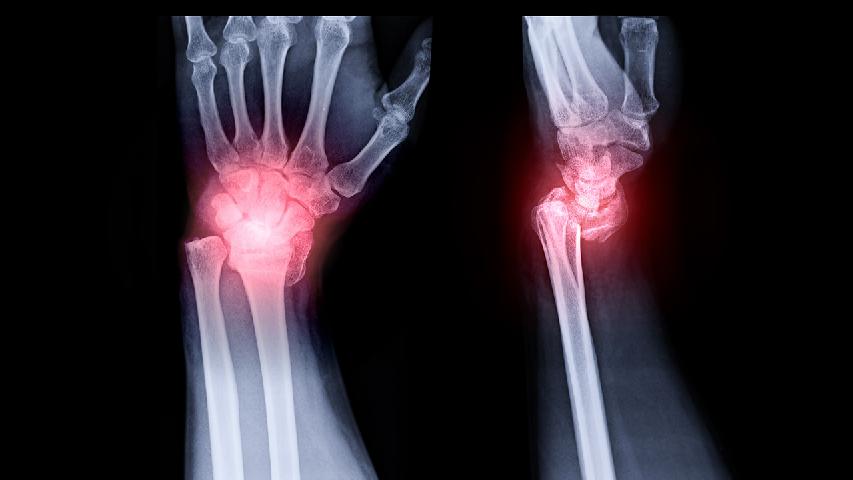

类风湿性关节炎的病因不是特别明确,可能是由于自身免疫或者是遗传感染,吸烟等因素导致的,和平时所处的环境关系并不大,积极的进行治疗是可以达到完全控制的效果的,并不会影响工作和生活。如果长期如此的话,最好还需要检查一下是否严重。

类风湿性关节炎起因有哪些

据专家介绍,类风湿性关节炎是一个与环境、细胞、病毒、遗传、性激素及神经精神状态等因素密切相关的疾病。类风湿性关节炎起因有哪些呢?下面就为大家详细的介绍一下,希望能够对大家有所帮助。类风湿性关节炎起因如下所示:细菌因素实验研究表明A组链球菌及菌壁有肽聚糖(peptidoglycan)可能为RA发病的一个持续的刺激原,A组链球菌长期存在于体内成为持续的抗原,刺激...